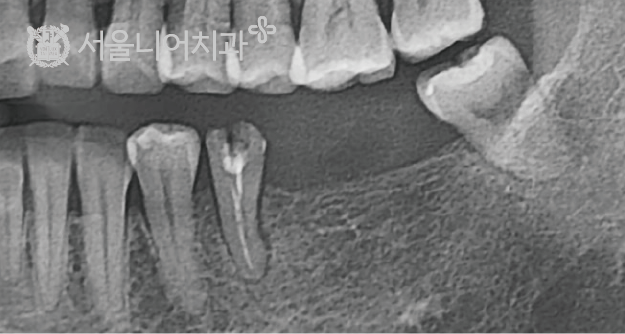

기존 임플란트가 망가지면서 발치를 하게되어 잔존 골이 많이 남지 않은 경우에도 신경손상의 위험성을 최소화하면서도 잔존골을 최대로 활용한 최적의 임플란트 식립이 가능합니다.